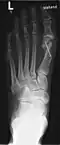

Röntgenbilder

-

Hammerzehen vor einer operativen Korrektur -